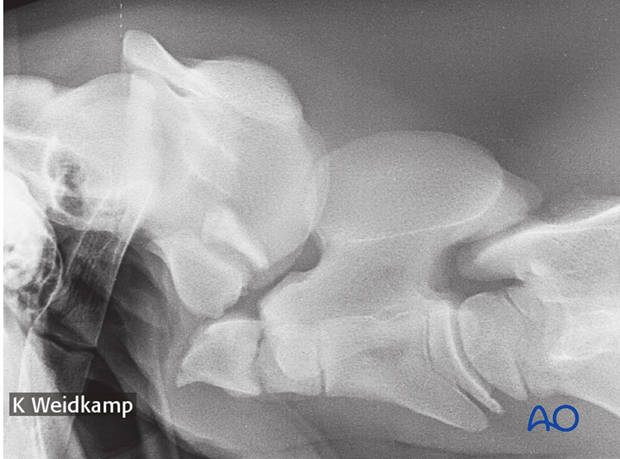

Fracture of the atlas vertebra.

Radiographs:

Radiographic examination: